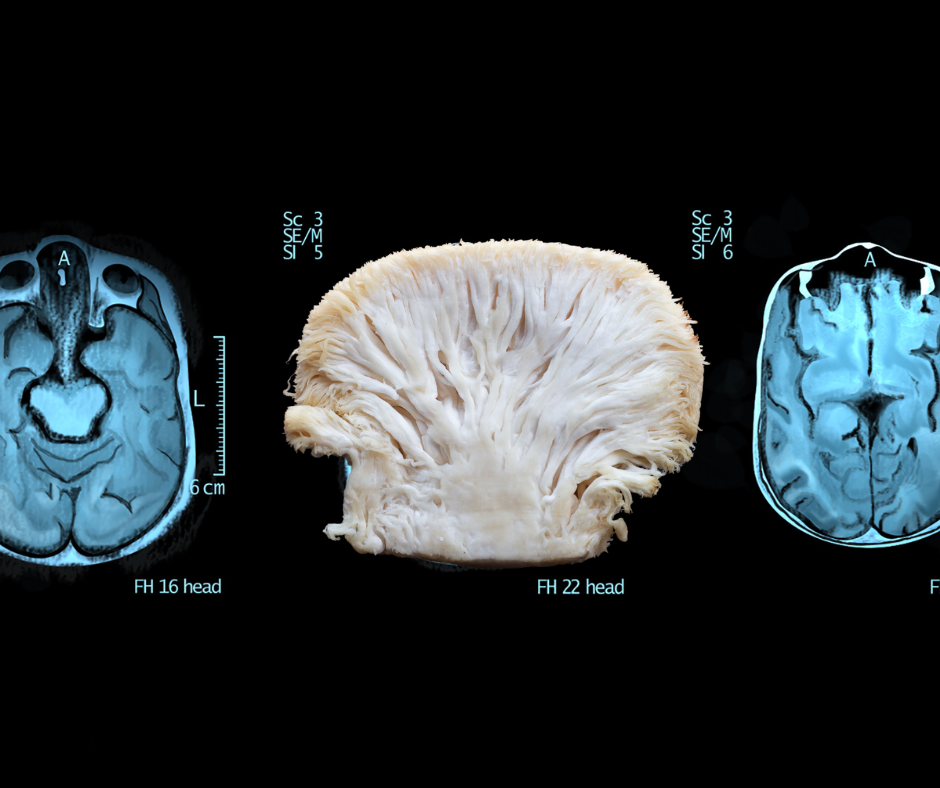

Lion’s mane mushroom has earned its reputation as a “smart mushroom” for a reason. It contains two key compounds—hericenones and erinacines—that stimulate the production of nerve growth factor (NGF), a protein essential for the growth and survival of neurons.

So yes, it’s brain food—but also supports the immune system, gut health, and even nerve repair. And, even cooler- if you cut it in half, it kind of looks like a brain!

Angela Ardolino, founder of CBD Dog Health and MycoDog, created the Senior Dog Study—a 90-day trial using her CLARITY mushroom extract and adaptogen blend tincture on dogs in their senior stage of life. The results? Honestly, they were pretty damn amazing.

Dogs in the study showed:

- Improved mental clarity and reduced cognitive dysfunction behaviors

- Better mobility and less stiffness

- Increased energy and engagement with their surroundings

- Improved sleep and calmer behavior

Angela’s CLARITY blend includes dual-extracted lion’s mane mushroom alongside other heavy hitters like reishi and cordyceps—but lion’s mane steals the show when it comes to cognitive health. The adaptogens in the blend include ashwagandha and bacopa monnieri, both of which are excellent for supporting immune, cognitive and neurologic function.

The results aren’t just anecdotal either—pet parents were filling out detailed weekly assessments and watching their dogs regain sparkle in their eyes and bounce in their step alongside hard data which was obtained from GPS tags on their collars.